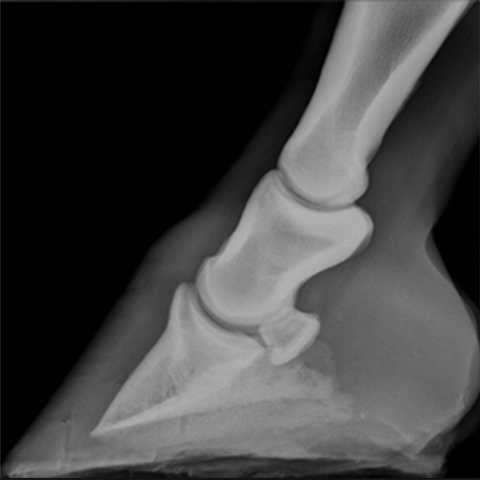

Radiology

Radiograph Consult

Our board-certified radiologists - including ACVR-EDI (Equine Diagnostic Imaging) and ECVDI–Large Animal diplomates - provide comprehensive written interpretations of radiographs in conjunction with each patient’s medical history. We serve a wide range of species, including alpacas, cattle, equine, goats, llamas, swine, and sheep.